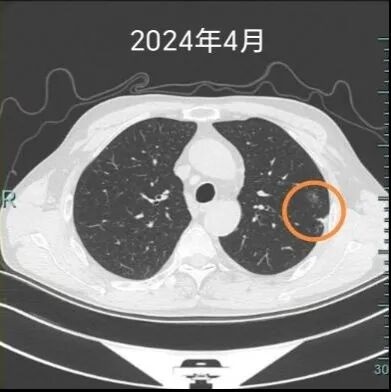

“除了戒烟,还要记得定期复查,有什么不舒服的也能及早治疗。”就这样,在术后两年的复查中,医生发现,杨先生的左上肺又出现了一个明显的实性结节,并有胸膜牵拉表现,提示恶性可能。这让杨先生再次来到该院心胸外科就诊。

“有些早期肺癌,就像埋在土里的种子。第一颗被我们挖掉了,但土壤里可能还藏着另一颗,或者因为长期吸烟造成的‘坏环境’,让新的种子在别处发芽了。”心胸外科专家团队用形象的比喻为杨先生解释了病情,安抚他焦虑的情绪。很快,又为他实施了胸腔镜下左上肺亚肺叶切除术,标本可见明显的胸膜凹陷,剖开可见两枚结节,术后病理明确诊断为腺癌。